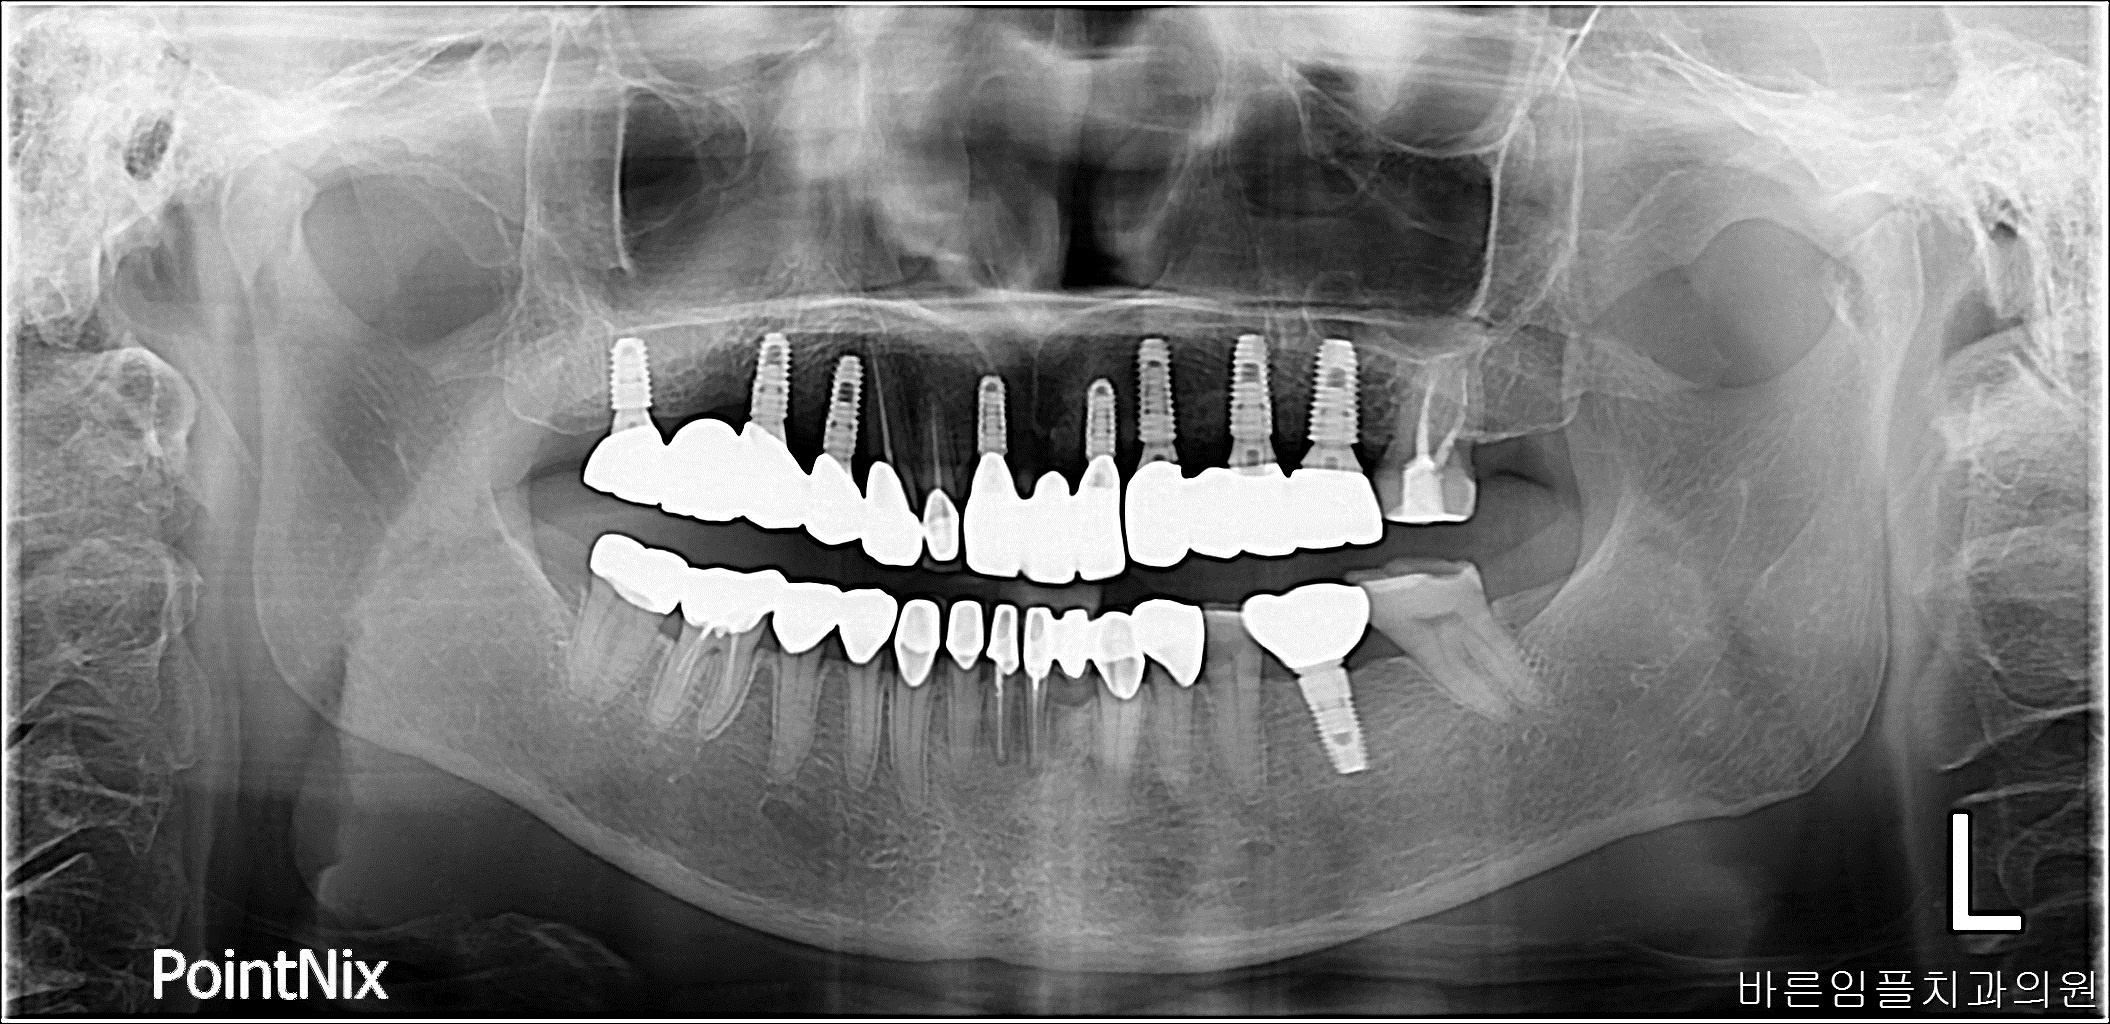

차ㅇㅇ / 수면임플란트 페이지 정보 작성일 23-10-27 17:06 2021-03-10 차ㅇㅇ Before 2023-03-16 차ㅇㅇ After 차ㅇㅇ / 수면임플란트 목록 다음글 이ㅇㅇ / 수면임플란트